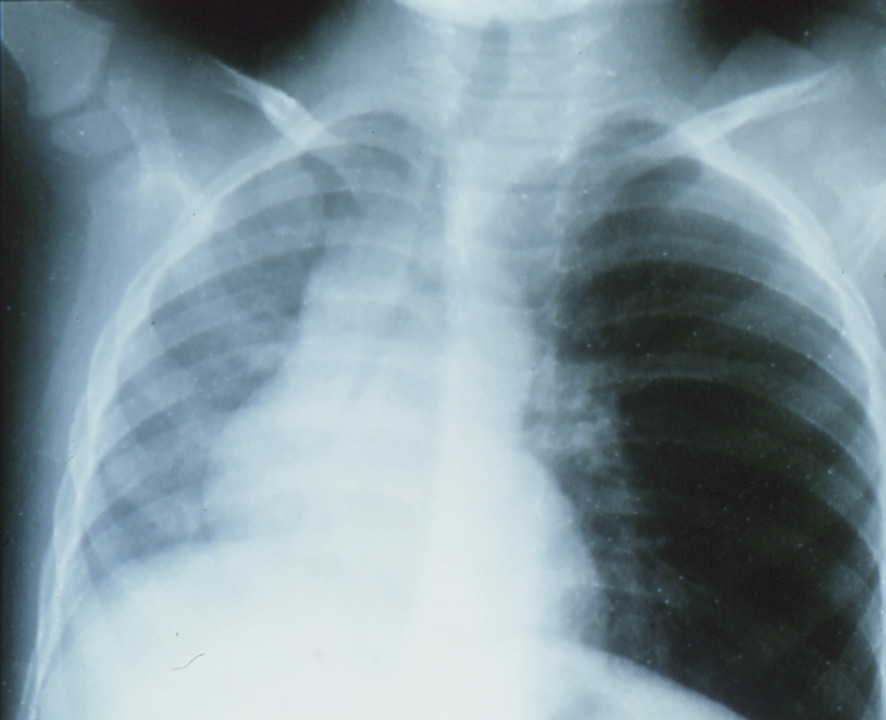

Si l’enfant après une période de toux brutale et de gêne respiratoire (syndrome de pénétration) respire à nouveau normalement, il faut néanmoins qu’il soit examiné : auscultation pulmonaire et radiographies du thorax en expiration et en inspiration (fig. 2 ).

Si l’enfant après une période de toux brutale et de gêne respiratoire (syndrome de pénétration) respire à nouveau normalement, il faut néanmoins qu’il soit examiné : auscultation pulmonaire et radiographies du thorax en expiration et en inspiration (